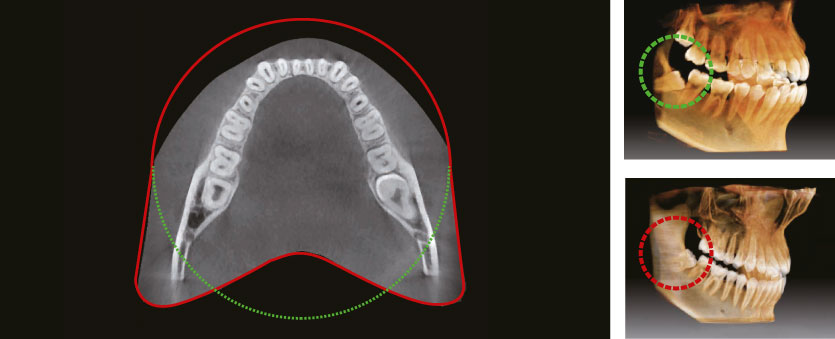

Анатомическое поле сканирования

Инновационное поле обзора компьютерном томографе Green Smart обеспечивает захват объема в форме зубной дуги, что обеспечивает попадание более широкой зоны интереса по сравнению с другими аппаратами с аналогичными по размеру полями обзора. Обычно, поле обзора 10x8,5 достаточно для визуализации 8-х зубов. В случае ретенированных 3-х моляров высока вероятность того, что корни зуба могут быть срезаны. "Арочный объем" исключает такую вероятность, демонстрируя скрытую область зубного ряда.